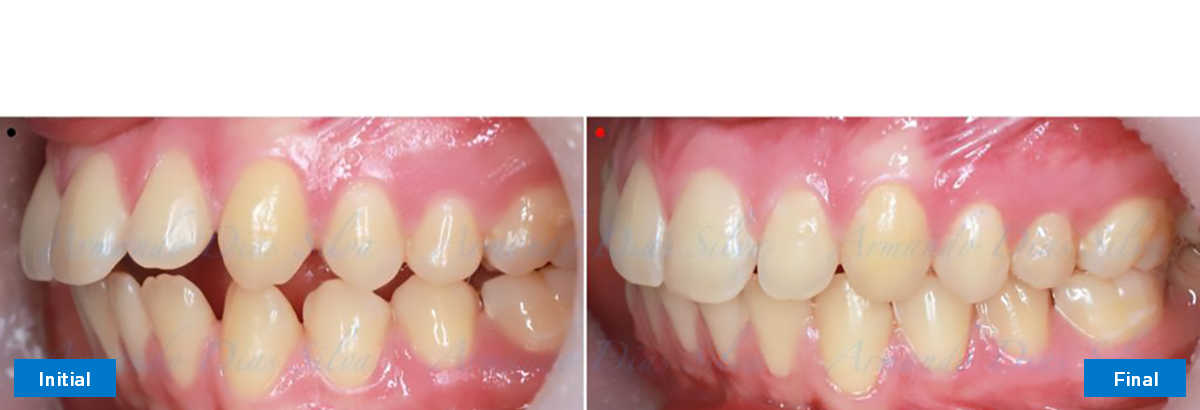

• Molares de clase II

• El primer molar superior derecho está en una posición más mesial que el primer molar superior izquierdo

• Orientación canina desfavorable

• Desrotar y distalizar los molares superiores

• Molares de clase I logrados con distalización y sin elásticos

• Sin cambios en la posición del cóndilo